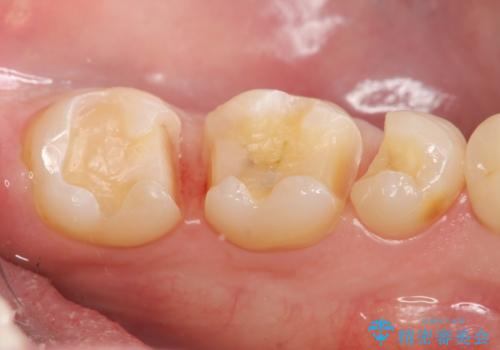

保険適応の白い詰め物レジンインレー下に再発した大きな虫歯治療

- 12万円 ゴールドインレー×2費用は治療当時の料金となります

ゴールドは見た目に難がありますが、歯を削る量がセラミックに比べて少ない・複雑な形にも追従しやすい・壊れにくいなどの利点があります。